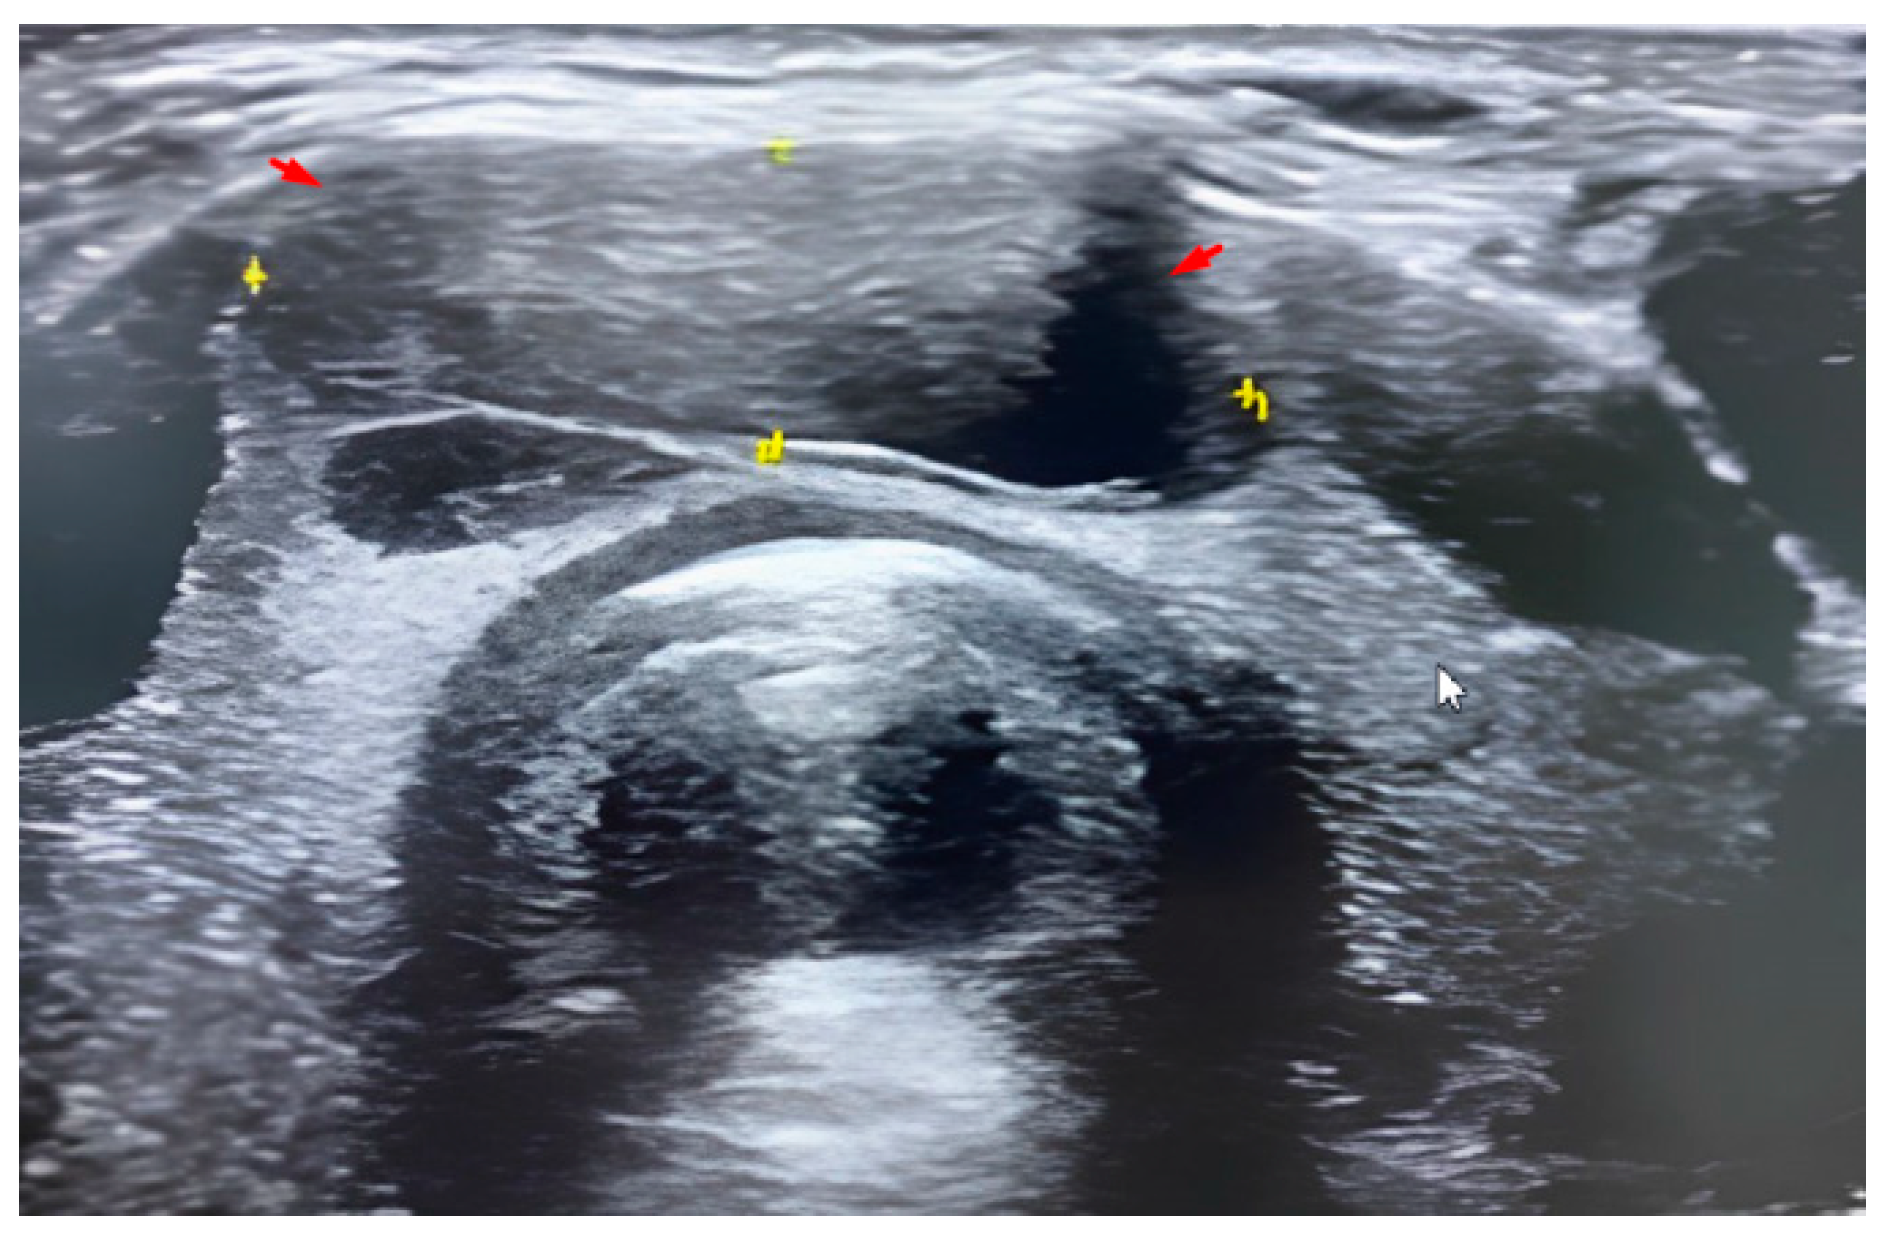

2.5. Radiological and Histological Examination

2.6. Methodology of FNA